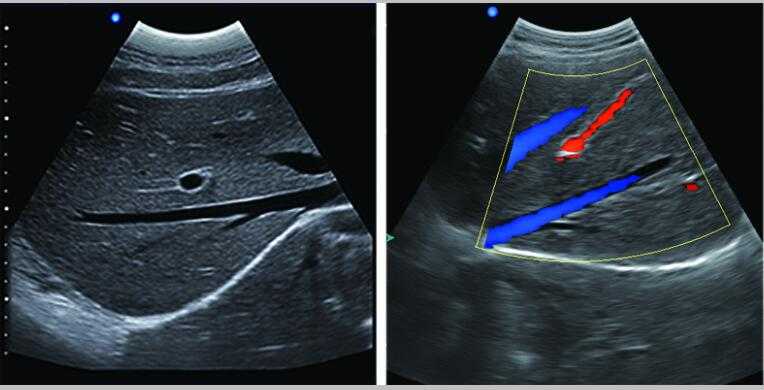

全數字彩色多普勒超聲診斷儀DW-PE522

彩色多普勒

采用智能圖像處理技術

1.組織諧波成像技術 2.噪聲抑制斑點技術 3.多波束并行處理技術等